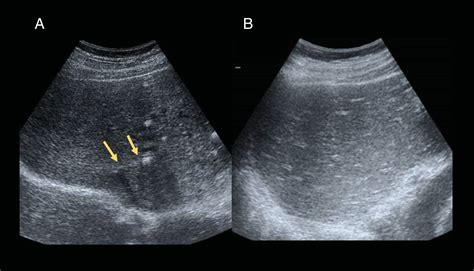

Cirrhosis is not an overnight occurrence; it is the final phase of chronic liver disease. It occurs when healthy liver tissue is replaced by scar tissue, or fibrosis, usually as a result of long-term inflammation. Common causes include chronic hepatitis B or C infection, prolonged alcohol consumption, non-alcoholic fatty liver disease (NAFLD), and autoimmune disorders.

As the scarring becomes more extensive, the liver’s ability to function diminishes. This leads to several systemic complications that drastically reduce quality of life. Common indicators that a patient may be a candidate for a liver cirrhosis liver transplant include:

• Ascites: The accumulation of fluid in the abdomen.